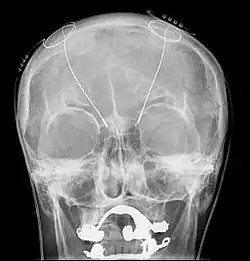

Электроэнцефалография (ЭЭГ) — один из ключевых неинвазивных методов исследования головного мозга, который характеризуется высоким временным разрешением, но низкой пространственной разрешающей способностью, особенно в сравнении с МРТ или инвазивными электродными методами. Из-за низкого пространственного разрешения (обычно не более 100 каналов), полученный сигнал является результатом суперпозиции активности крупных популяций нейронов, а значит, является удобным методом для нахождения и исследования синхронизированных коллективных режимов в сетях головного мозга. Синхронизация достаточно большой популяции нейронов обычно производит глобальные колебания, которые и записываются электродами электроэнцефалографа.